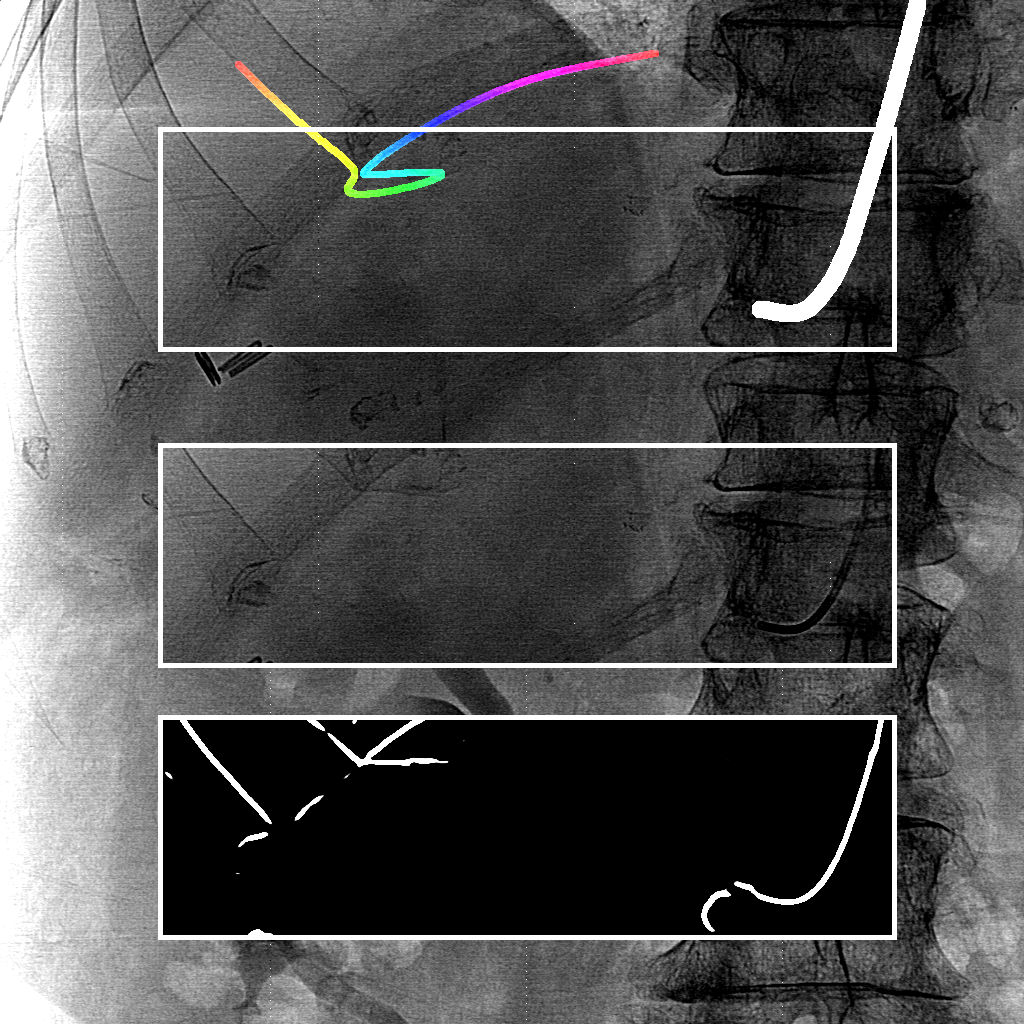

We evaluate using the tip distance error (i.e. the distance between the annotated catheter tip and the tip of the segmented catheter), and the average distance between the manually segmented catheter and the automatically segmented catheter. Figure 3 shows the tip and catheter distances results. We compute the precision of the tip between consecutive frames. The median, average, minimum and maximum of the standard deviation per sequence of the tip distance error are respectively 0.7 mm, 4.9 mm, 0.1 mm and 55.7 mm. Five examples of segmentation are shown in Figure 4. In the third frame, the segmentation is going too far and follows part of the vertebrae. The fourth frame misses the proximal part of the catheter. The last frame is the only sequence with significant false positives. It is less noisy because it has been acquired with higher radiation dose. The neural network was not trained for such sequence.

We proposed a fully automatic method to segment catheter on 2D X-ray fluoroscopic images using CNNs. The segmentation on testing data gives a median tip distance error of 0.9 mm and a median centerline distance error of 0.2 mm where 85% of the frames have less than 1 mm of centerline distance error. We note that the distance errors are in mm at the X-ray detector scale. The real distance errors at the patient scale are smaller.

Very few images have false positives after the CNN segmentation. Therefore, we can use simple criteria to extract the catheter centerline from the CNN segmentation. The results show that it works well and can handle self-intersections. The main problem in the extracted catheters are sometimes large gaps in the segmentation due to false negatives. As a consequence, occasionally the proximal part of the catheter is missing. With a larger training set, the model is expected to generalize better.